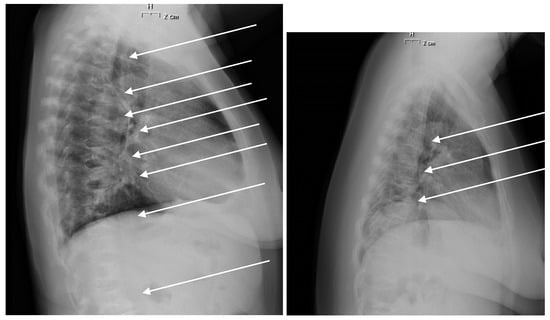

- Genant, H.K.; Jergas, M.; Palermo, L.; Nevitt, M.; Valentin, R.S.; Black, D.; Cummings, S.R. Comparison of semiquantitative visual and quantitative morphometric assessment of prevalent and incident vertebral fractures in osteoporosis The Study of Osteoporotic Fractures Research Group. J. Bone Min. Res. 1996, 11, 984–996. [Google Scholar] [CrossRef]

- Serarslan, Y.; Kalaci, A.; Ozkan, C.; Dogramaci, Y.; Cokluk, C.; Yanat, A.N. Morphometry of the thoracolumbar vertebrae in sickle cell disease. J. Clin. Neurosci. 2010, 17, 182–186. [Google Scholar] [CrossRef]

- Guglielmi, G.; Diacinti, D.; van Kuijk, C.; Aparisi, F.; Krestan, C.; Adams, J.E.; Link, T.M. Vertebral morphometry: Current methods and recent advances. Eur. Radiol. 2008, 18, 1484–1496. [Google Scholar] [CrossRef]

- Ruosi, C.; Liccardo, S.; Rubino, M.; Colella, G.; Di Somma, C.; Colao, A. Importance of spinal deformity index in risk evaluation of VCF (vertebral compression fractures) in obese subjects: Prospective study. Eur. Spine J. 2013, 22, S945–S949. [Google Scholar] [CrossRef]